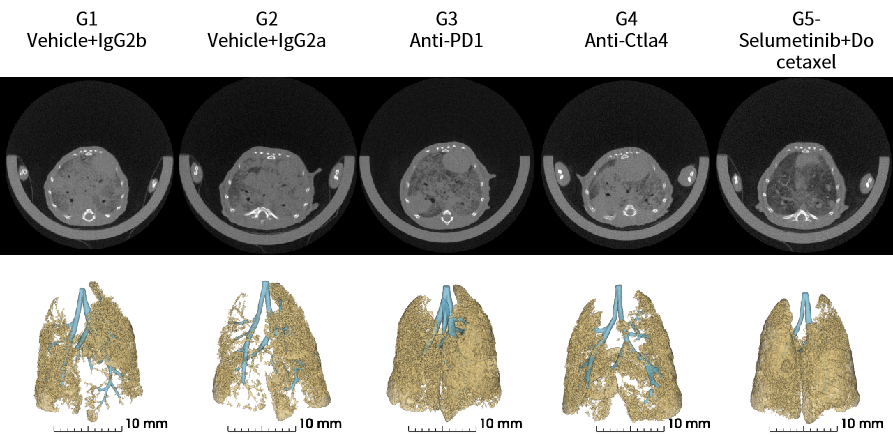

图2. Stk11/EGFP/Kras-LSL-G12D瘤块来源细胞系皮下移植造模的抗肿瘤药效评价。

图3. Stk11/EGFP/Kras-LSL-G12D瘤块来源细胞系原位移植造模的抗肿瘤药效评价。